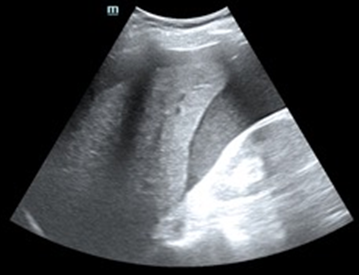

Tras varias horas en observación el paciente comienza con tendencia a la hipotensión. Permanece en observación y monitorización persistiendo hipotensión arterial con buena ventilación bilateral en la auscultación pulmonar. En la exploración abdominal presenta dolor y defensa a la palpación profunda en hipocondrio izquierdo. Se realiza Ecografía clínica a pie de cama del paciente descartando hemoneumotótax y derrame pericárdico; al explorar el abdomen se objetiva líquido libre en espacio de Morrison y eje espleno renal, con imagen compatible con rotura del parénquima esplénico. Gasométricamente se objetiva anemización con caída de cifras de Hb de 15,7 g/dl en análisis inicial a 13,8 g/dl. Se solicitan pruebas cruzadas, se reservan hemoderivados y se contacta con cirugía para traslado del paciente a quirófano.